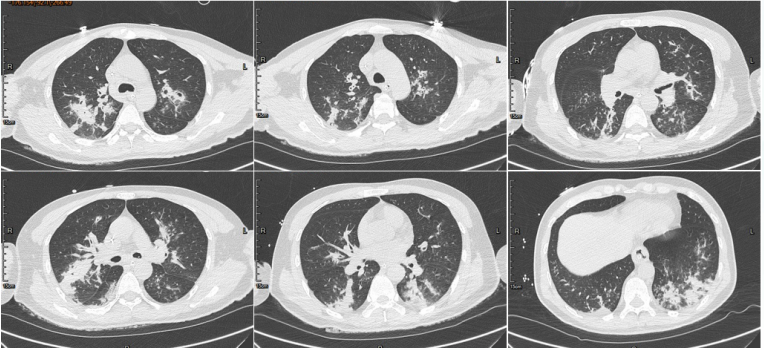

胸部CT(2022-01-10):沿支气管血管束分布的大片状实变影及结节影,胸膜下楔形影和空洞影,可见支气管充气征(图5)

图片

5  病例1胸部CT